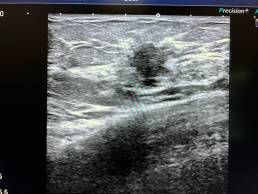

Femme de 52 ans , mammographie de dépistage.

MammoscreenTM pointe une lésion rétromamelonnaire du sein droit.

La biopsie confirme un carcinome canalaire infiltrant SBR 2, R+